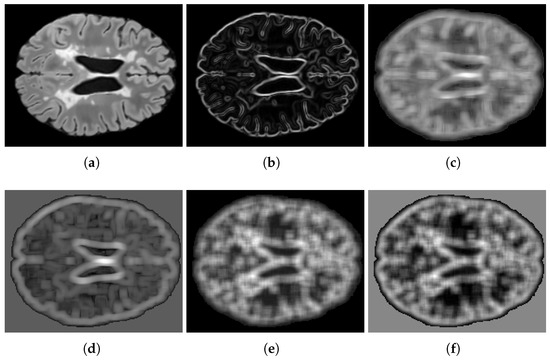

Figure 2. Feature visualization: (a) FLAIR intensity, (b) gradient magnitude, (c,d) GLCM principal components 1–2, (e,f) GLRLM principal components 1–2.

Texture features are derived from square areas centered around each voxel. For gradient features, 3 × 3 neighborhoods are used, whereas larger 9 × 9 neighborhoods are utilized to calculate the 13 GLCM and 11 GLRLM features. To address the curse of dimensionality in precision matrix estimation from limited samples, only the first two principal components of the GLCM and GLRLM features were retained, effectively capturing over 90 % of the total variance. Empirical analysis demonstrated that incorporating additional principal components did not improve the segmentation performance and often led to instability in precision matrix estimation. Figure 2 illustrates these features, omitting the spatial coordinates h and w.